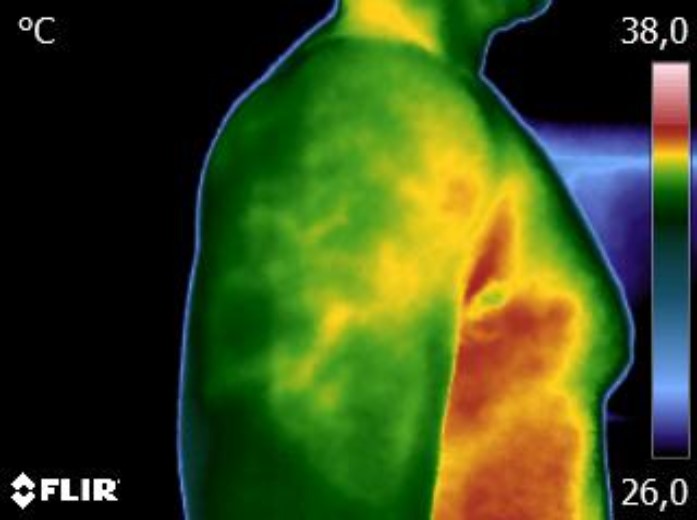

Caros colegas fisioterapeutas e terapeutas ocupacionais, vocês sabiam que, por meio do estudo da Termofuncional, é possível identificar alterações térmicas […]

Caros colegas fisioterapeutas e terapeutas ocupacionais, vocês sabiam que, com o estudo da técnica Termofuncional, é possível identificar alterações térmicas […]